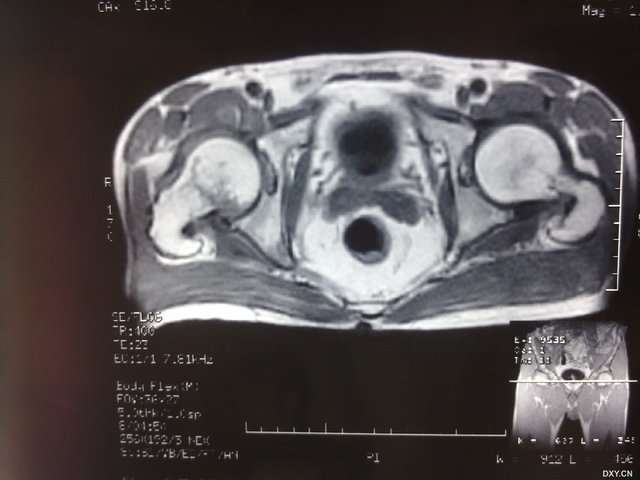

男性,56岁,摔伤至右髋部疼痛2小时入院。X片示未见明显骨折征象。但查体见右腹股沟压痛明显。当时考虑右髋部软组织挫伤。今查MRI示右股骨颈骨折。呵呵。